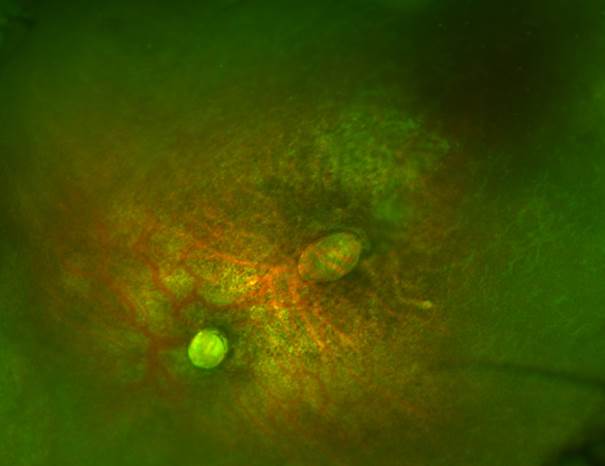

La valoración oftalmológica reportó rechazo a la luz en ojo derecho, sin fijación ni seguimiento de objetos, nistagmo y exotropía de 45º K; en retina se presentaron zonas de atrofia coriorretiniana de predominio macular superior y peripapilar así como atrofia del nervio óptico (figura 1); en el ojo izquierdo también presentaba rechazo a la luz, sin fijación ni seguimiento de objetos, nistagmo, iris con corectopia, retina con atrofia coriorretiniana severa y cicatriz macular de dos diámetros de disco y de forma oval, así como una aplasia total del nervio óptico (figura 2).

En cuanto a las características oftalmológicas descritas, puede haber baja agudeza visual, la cual puede ser independiente de las manifestaciones estructurales, ya que se relaciona más con el daño en el sistema nervioso central. El rango de visión puede ir desde una pérdida visual leve a la no percepción de luz. Por otro lado, se ha descrito nistagmo y estrabismo, subluxación del cristalino, coloboma de iris, anomalías del nervio óptico, de la mácula y de la retina periférica.17 El nervio óptico puede estar hipoplásico o atrófico; la mácula presenta pérdida del reflejo foveolar, moteado pigmentario, áreas circulares demarcadas de atrofia coriorretiniana y maculopatía pigmentaria. En la retina periférica se describe tortuosidad vascular, terminación abrupta de la vasculatura, hemorragias subrretinianas por fuera de la mácula, cambios pigmentarios asociados con lesiones atróficas blanquecinas que parecen “huellas de oso polar” y cicatrices coriorretinianas de aspecto colobomatoso.14 También se han descrito casos de glaucoma congénito.18 Hasta donde sabemos, no existen reportes previos con aplasia total del nervio óptico como se encontró en la paciente.

En este caso se presentó a una paciente proveniente de una zona endémica, cuya madre tuvo diagnóstico de Zika confirmado por laboratorio durante el primer trimestre del embarazo. El ultrasonido prenatal demostró dos de las características compatibles con Zika congénito: retraso en el crecimiento intrauterino y microcefalia. Postnatalmente se confirmó la microcefalia, retraso global del neurodesarrollo con crisis convulsivas de difícil control, piel cabelluda redundante, hipertonía y disfunción a la deglución. Los hallazgos oftalmológicos fueron consistentes con zonas de atrofia coriorretiniana, atrofia y aplasia del nervio óptico, así como cicatriz macular. La tomografía craneal también mostró datos duros compatibles con Zika congénito, como el adelgazamiento de la corteza, la ventriculomegalia y las calificaciones subcorticales difusas. Si bien las pruebas de laboratorio para Zika fueron negativas, la revisión realizada en la literatura refiere que hay que correlacionar la clínica y las pruebas de laboratorio maternas con la clínica y la serología del recién nacido, y un 10% de los casos pueden ser seronegativos. En este caso, el diagnóstico se estableció por el cuadro clínico y las pruebas de laboratorio maternas correlacionadas con el cuadro clínico de la paciente.